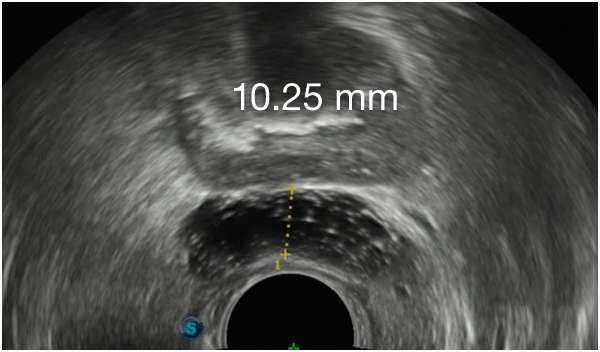

Implant Symmetry RESULTS6 >95%

Pivotal Trial Patients; % of implants centered on prostate midline

First Barrigel Cases - Consecutive Patients (Same Day)

TRUS images courtesy of Daniel R. Welchons, MD

Urologist; New York, United States

DR. WELCHONS’ INJECTION TECHNIQUE

IN RECTAL SPACING

STABILITY MATTERS

IN RECTAL SPACING STABILITY

MATTERS

PATIENT EXAMPLE SHOWING

STABLE SEPARATION DURING RESORPTION

MEAN PROSTATE-RECTUM SEPARATION (DIMENSIONAL STABILITY)